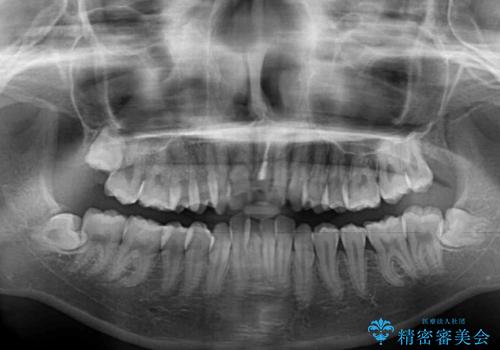

口元を積極的に引っ込めるために、上下左右の小臼歯を4本抜歯することとしました。

右上前から2番目の歯が欠損しているため、①矯正治療により欠損部にスペースを作りインプラント補綴を行って前歯を左右対称に揃える、②左右非対称となるが、欠損補綴を行わずに排列する、のいずれかとなりますが、患者様と相談の上②にて矯正治療を行うこととしました。

変則的な歯列であったため、奥歯がしっかりと咬み合うのか、前歯はしっかりと排列できるのかと不安ではありましたが、結果としてはきれいに整った歯列にて終了することができました。